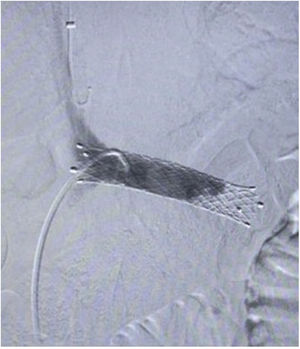

Surgical techniqueThe principles applied were urgent LRV pressure control, treatment of the hematuria, venous drainage derivation and congestive pelvic syndrome origin resolution. All the patients remain 24h postoperative in hospital observation. The repair was performed via endovascular access, after local anesthesia and sedation. The right common femoral and the left internal jugular vein was punctured with ultrasound guide and a 6F introducers sheath were inserted. The LRV was catheterized with a Cobra 2 5F diagnostic catheter and phlebography was performed. This confirmed critical stenosis of the LRV and the pelvic varicose veins on the left, with a dilated left gonadal vein (Fig. 1). The stenosis pressure gradient was measured in all patients. Through the internal jugular access, balloon LRV angioplasty was performed (Fig. 2) and then deployment of a e-Luminex self-expanding nitinol bare metal arterial stent (10–12mm×40mm) (Figs. 3 and 4) was performed resolving the NCS (Fig. 5). Additionally, identified pelvic varicose veins were embolized using Concerto coils (20mm×50mm) through the basilic vein using a multi-purpose catheter. No dietary restrictions were imposed, and oral food intake was initiated in the first 3 postoperative hours. No need for a postoperative ICU. Postoperative anticoagulation for 6 months using rivaroxaban and then switching to salicylic acid for another 6 months was prescribed to all patients. The postoperative patients follow-up was performed using Doppler ultrasound in the 6 months and physical examination in all face-to-face clinical outpatient consults.